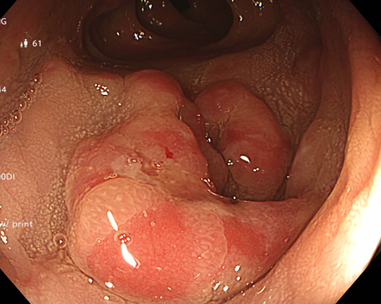

Kết quả nội soi dạ dày: Viêm teo niêm mạc dạ dày (C2 theo Kimura), dị sản ruột và có vi khuẩn H.pylori dương tính với test Urease từ mảnh sinh thiết qua nội soi.

Hình 1: Hình ảnh nội soi dạ dày

Kết quả nội soi đại tràng: có 3 polyp đại tràng (Paris Is, Kudo IIIL) (đã được cắt polyp qua nội soi), đại tràng sigmoid đã cắt một phần, tổn thương lồi đại trực tràng dạng polyp không cuống, ranh giới rõ, bề mặt màu hồng, có nhiều polyp có lớp nhầy ở trên bề mặt và thấy có hình ảnh da gà xung quanh tổn thương. Trên hình ảnh M-NBI thấy các tổn thương có các tuyến giãn nhẹ nhưng còn đều, mạch máu giãn nhẹ, chưa có biến đổi hình dạng --> đã tiến hành sinh thiết

Hình 2: Hình ảnh nội soi đại tràng